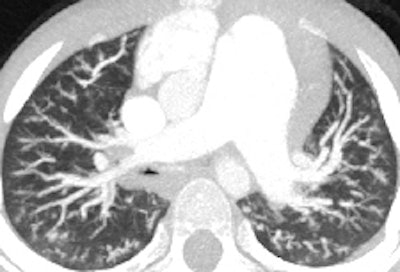

Retrospective ECG-gated study on a 5 year old with severe pulmonary hypertension. The CT images show dilated pulmonary arteries (top left). There is right atrial and ventricular dilatation with hypertrophy and bowing of the interventricular septum into the left ventricle (arrow, top right). There is abnormal arborization and angulation of the peripheral pulmonary arteries (top right, bottom), with multiple peripheral centrilobular nodules with perilesional ground-glass attenuation. Features are in keeping with pulmonary capillary hemangiomatosis.